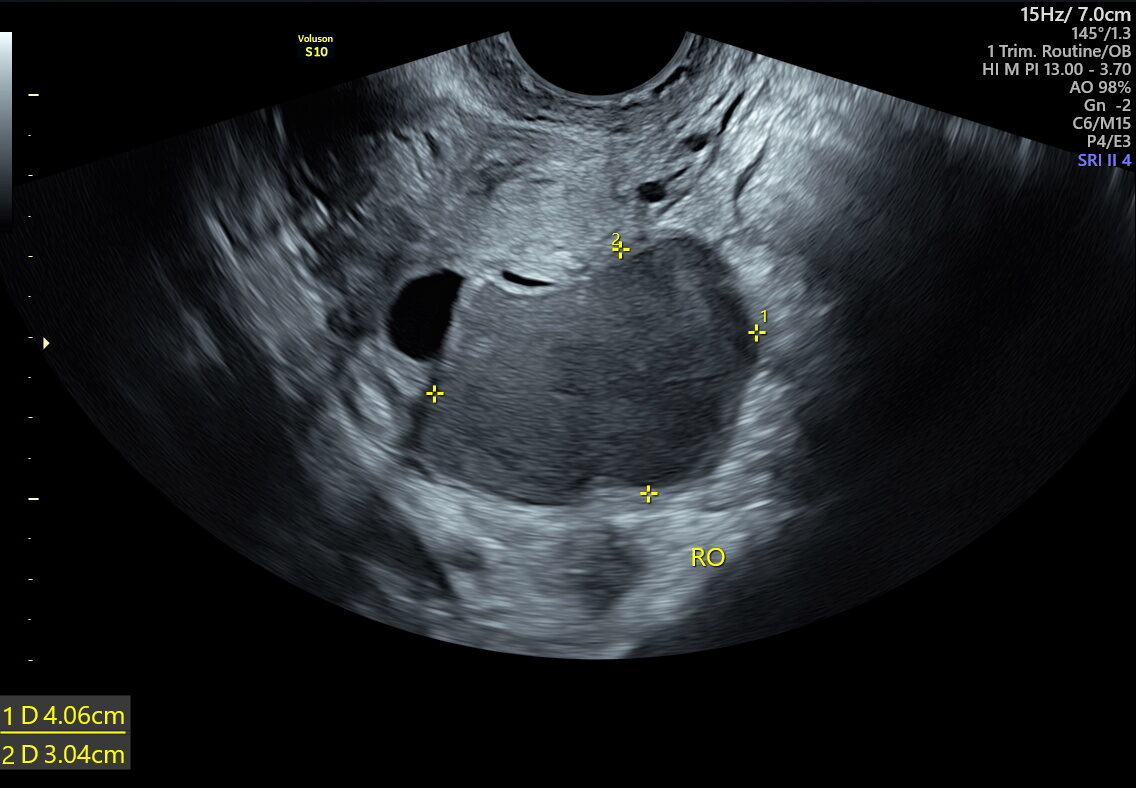

Traditional ultrasounds can miss small or deep infiltrating endometriosis. Advanced gynecological ultrasound, however, combines high-frequency probes, 3D/4D imaging, and specialized Doppler evaluation to provide detailed visualization of the uterus, ovaries, and pelvic structures.

- Ovarian endometriomas (chocolate cysts)

The diagnostic power of advanced gynecological ultrasound in Kolkata lies in its precision. Our fetal medicine and gynaecology imaging experts perform targeted assessments focusing on:

- Pelvic Adnexia scanning to locate deep lesions

- Ovarian mobility and sliding sign tests to detect adhesions